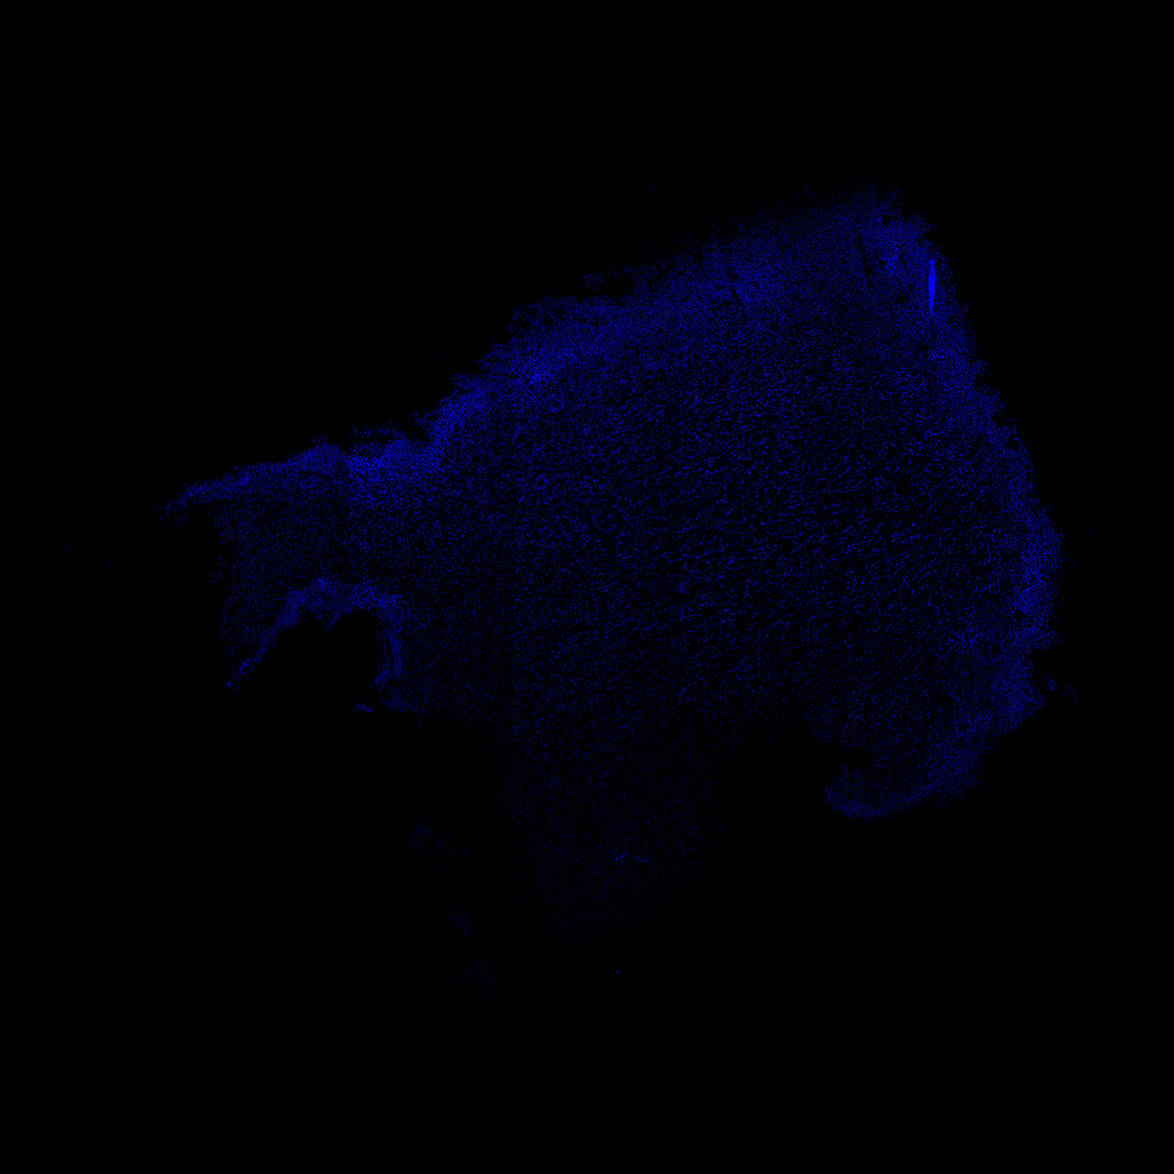

DAPI

6PCW human midbrain